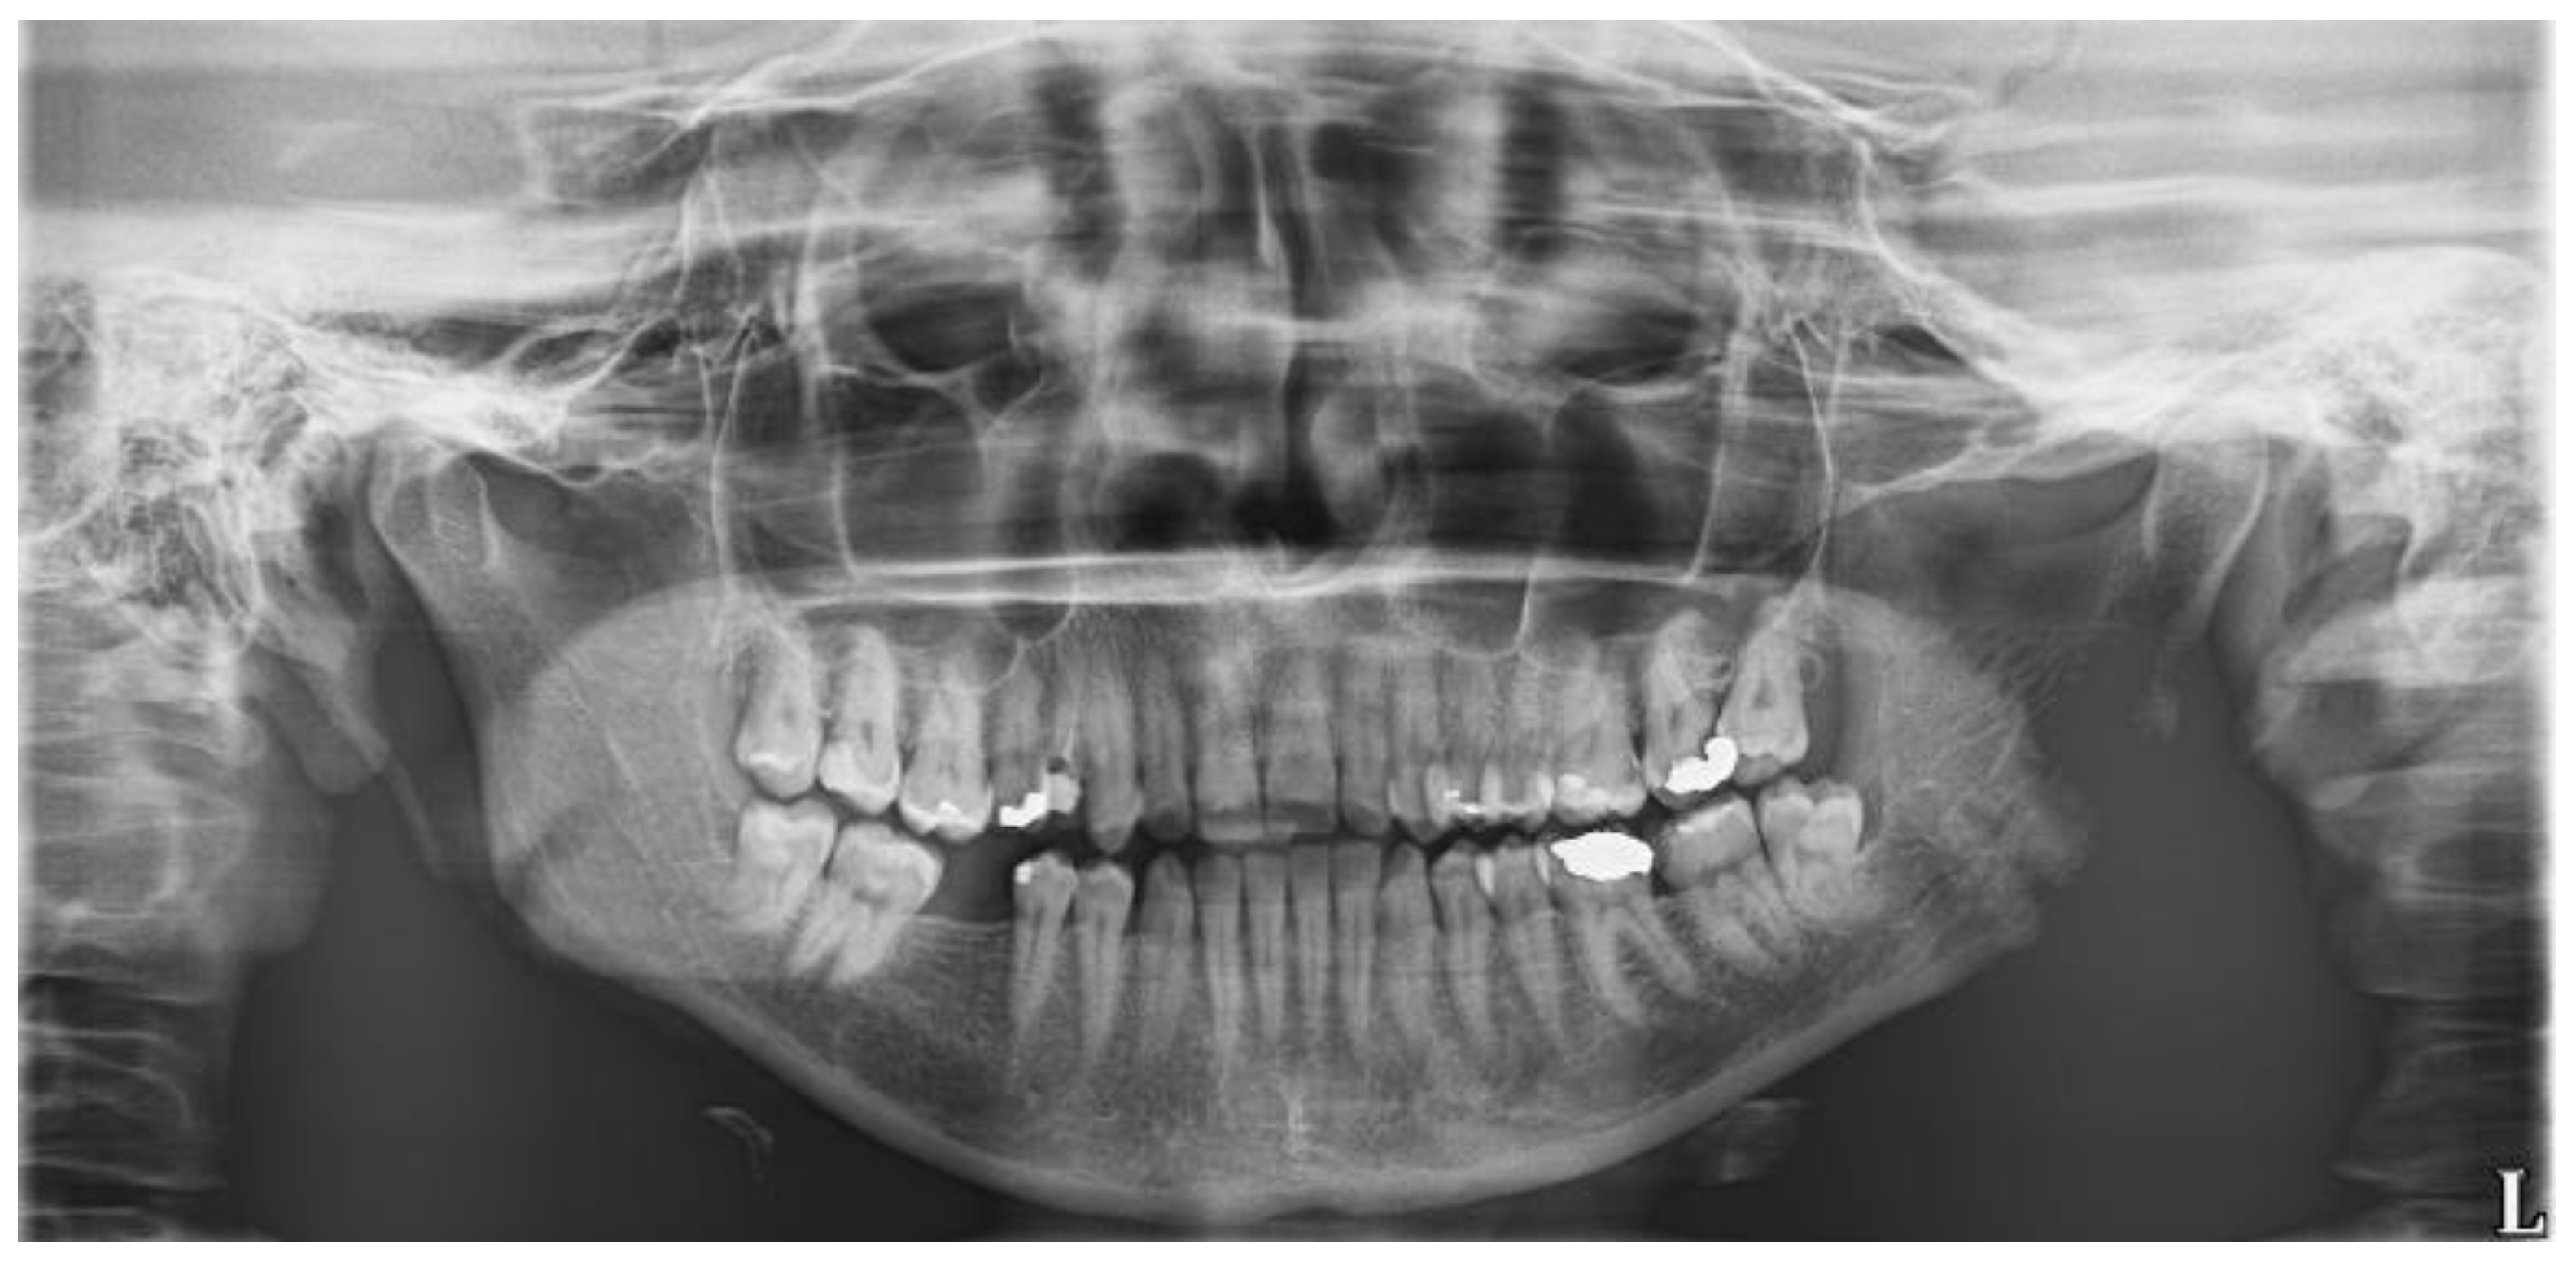

An 18-year-old female patient underwent a transalveolar extraction of an impacted tooth No. 38. She declared increased stomach pH, but no other diseases, no permanent medication, no allergies, and she smoked five cigarettes a day. The reason for extraction was repeated pain and pressure in the bone in the area of this tooth and a burnout around the tooth crown visible in the orthopantomogram (OPG) (Figure 2). Before the extraction, there was no pain nor swelling. According to the surgeon, the extraction was difficult and took approximately 30 min. Peroral antibiotics were prescribed—phenoxymethylpenicillin 1.5 million international units (MIU) t.i.d.

Figure 2. The orthopantomogram of the patient 1. Tooth No. 38 is semi-impacted in a mesially inclined, almost horizontal position. There is a burnout around the crown of the tooth.